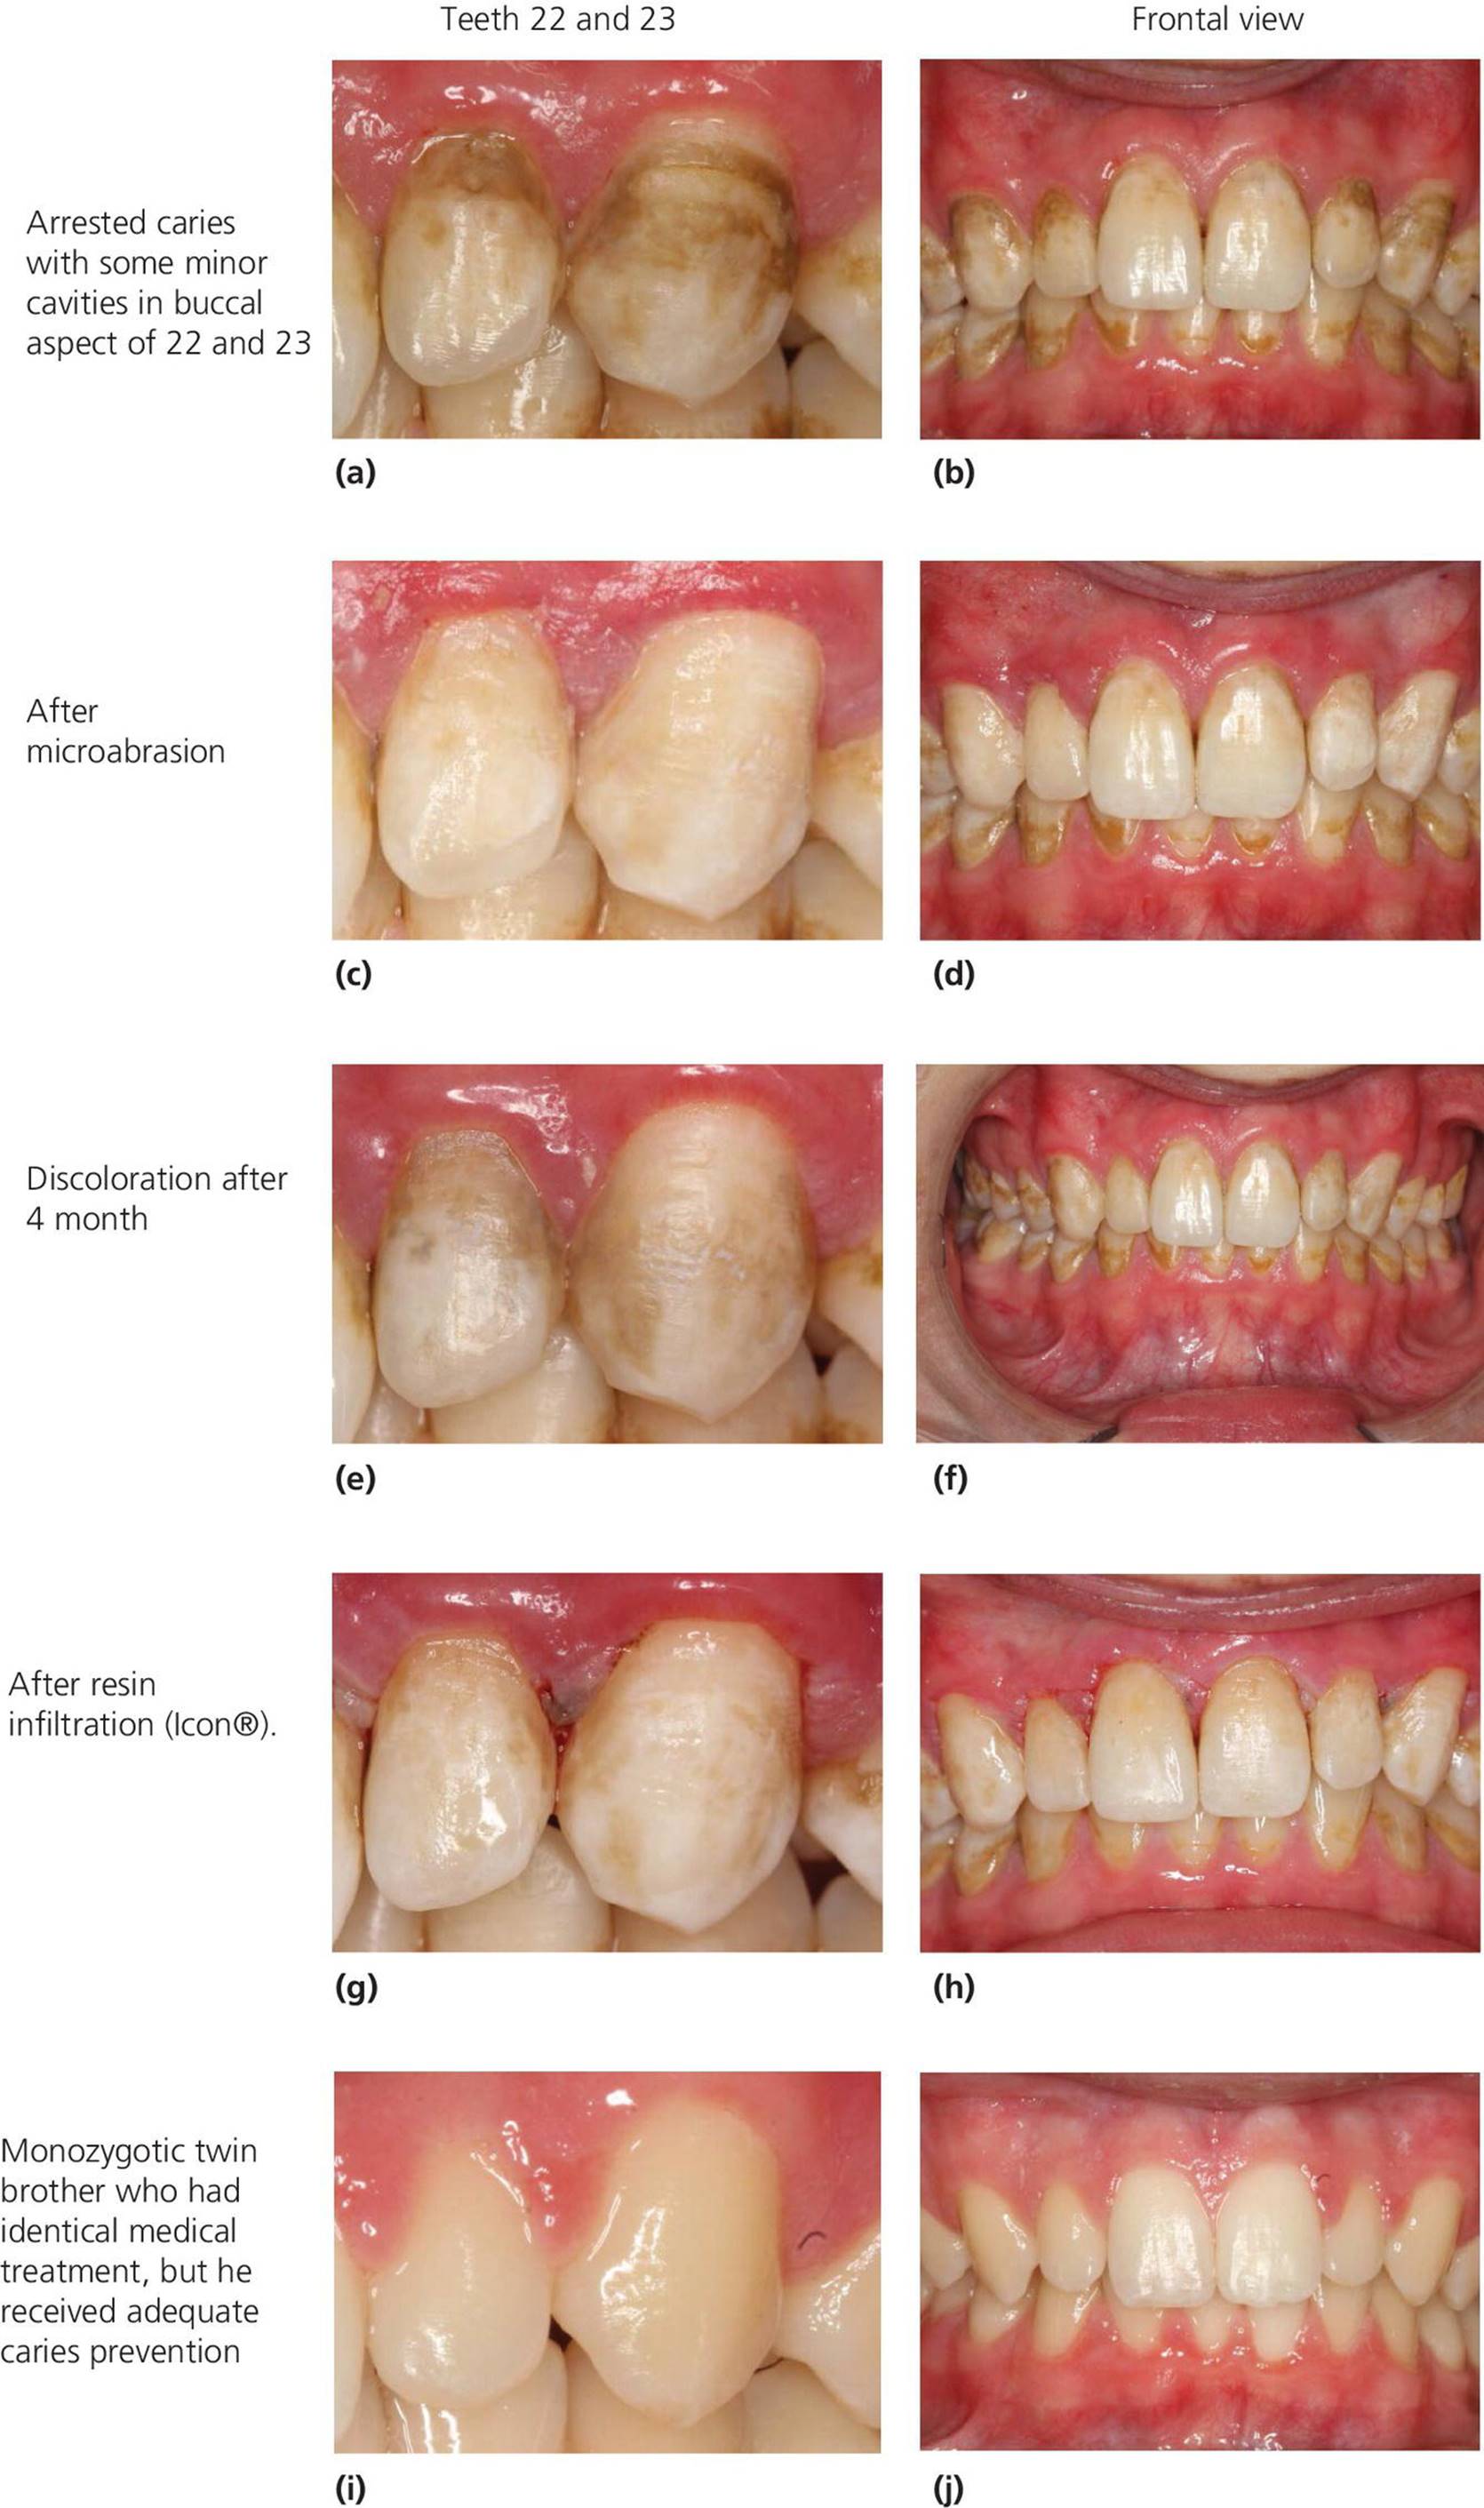

Diagnosis And Management Of Dental Caries - Pediatric Dentistry - A

caries pediatric dental diagnosis dentistry clinical teeth cavities approach treatment lesions after management discoloration properties fluoride fissures based 3ed releasing

12: Diagnosis And Management Of Dental Caries | Pocket Dentistry

caries dental dentistry clinical diagnosis icdas management pediatric surfaces tooth lesion smooth teeth occlusal enamel criteria grading pit severity fissure